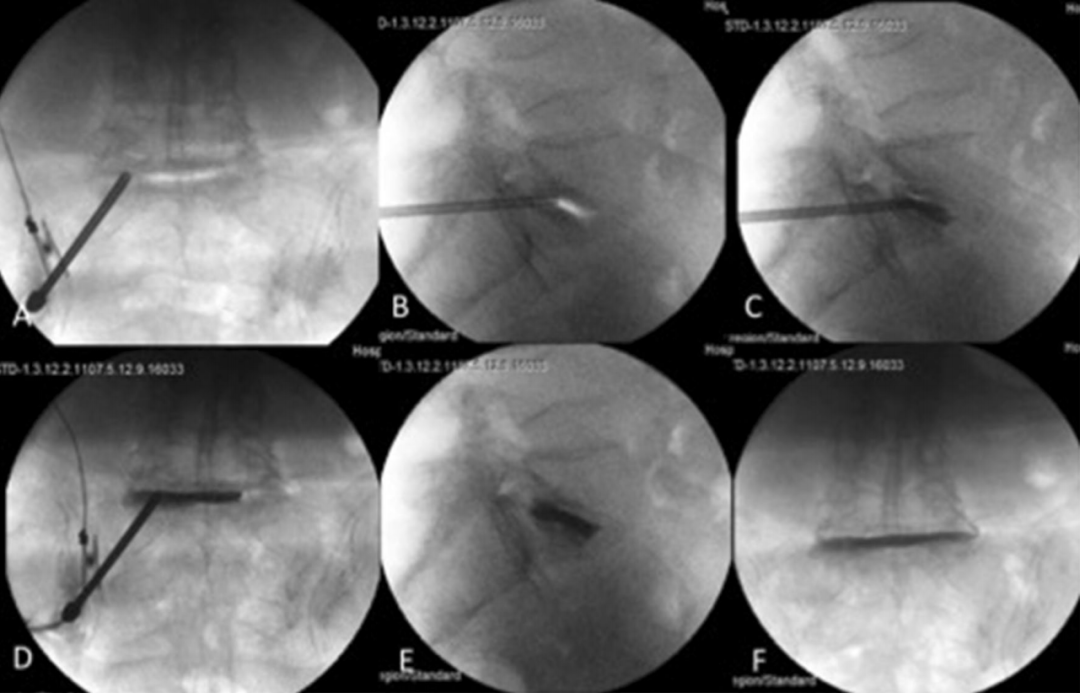

图: PCD术中图像a: 向椎间盘间隙插入Jamshidi 针; b: 针在正位时的位置; c,d: 将K-wire 插入Jamshidi针内; e,f: 插入椎体成形术套管针; g,h:PMMA骨水泥填充椎间盘; i,j: 术后情况

图: 左图为PLD(先),右图为PCD(后)